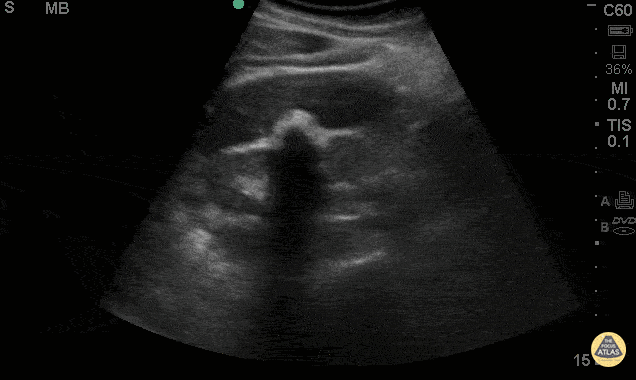

Biliary - Wall Echo Shadow

38 y/o F presented with abdominal pain, nausea & vomiting. POCUS shows the WES (Wall-Echo-Shadow) sign. This shows a curvelinear hyperechoic line representing the gallbladder wall, followed by a thin hypoechoic line representing a small amount of bile, then a curvelinear hyperechoic line, followed by acoustic shadowing. This sign is seen when the gallbladder has either a large gallstone or multiple small gallstones in a contracted gallbladder taking up the extent of the lumen. Sometimes this sign is misinterpreted as an air filled loop of adjacent bowel. Jaramillo, Juliana MD; Shah, Rushabh MD; Maurelus, Kelly MD - Kings County Emergency Medicine